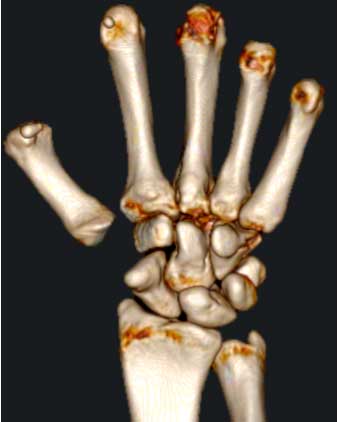

La Rizartrosis, o artrosis de la raíz del pulgar, es la lesión degenerativa más frecuente en la mano debida al desgaste progresivo de la articulación entre el trapecio y el primer metacarpiano.

Al observar la mano del paciente, casi siempre veremos ligera deformidad en la base del pulgar.

Al explorarle, los movimientos de la articulación entre el trapecio y el metacarpiano serán dolorosos.

Radiológicamente, el espacio entre el trapecio y el metacarpiano ha disminuido.

Dependiendo del grado de evolución de la rizartrosis, esta disminución del espacio articular puede evolucionar desde un ligero “pinzamiento” hasta una completa destrucción de la articulación.